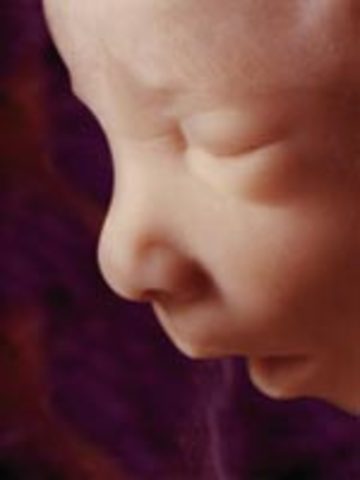

• Week 12

Week 12

Fetus' face is starting to look like a human baby. Nails start appearing. Pancreas begins to function and fetus can hiccup and suck thumb